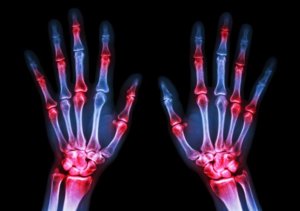

РА является системным аутоиммунным заболеванием с преимущественным поражением мелких суставов, что вызывает боль и скованность в них. Эрозивно-деструктивный процесс в суставах неуклонно прогрессируют, что в конечном итоге приводит к нарушению подвижности и деформации. РА можно заболеть любом возрасте, но чаще страдают люди от 40 до 60 лет, около 75% из которых являются женщины. РА считается хроническим заболеванием с большим разнообразием вариантов течения: как медленно, так и быстро оно может неуклонно прогрессировать, может перейти в длительную ремиссию, а иногда и полностью исчезнуть. Без лечения существенно сокращается продолжительность жизни, а также возможна серьезная инвалидизации.

Для РА характерно симметричное поражение мелких суставов

- Болезненные, теплые на ощупь, опухшие суставы (чаще всего верхней конечности).